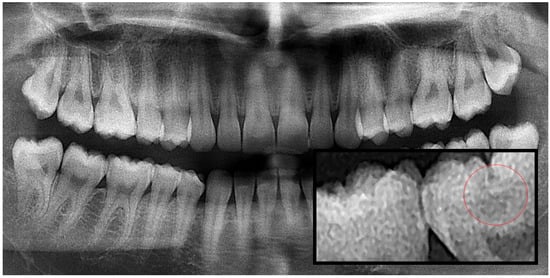

Figure 3.

Panoramic radiography and segmented secondary caries, red circle show the caries.